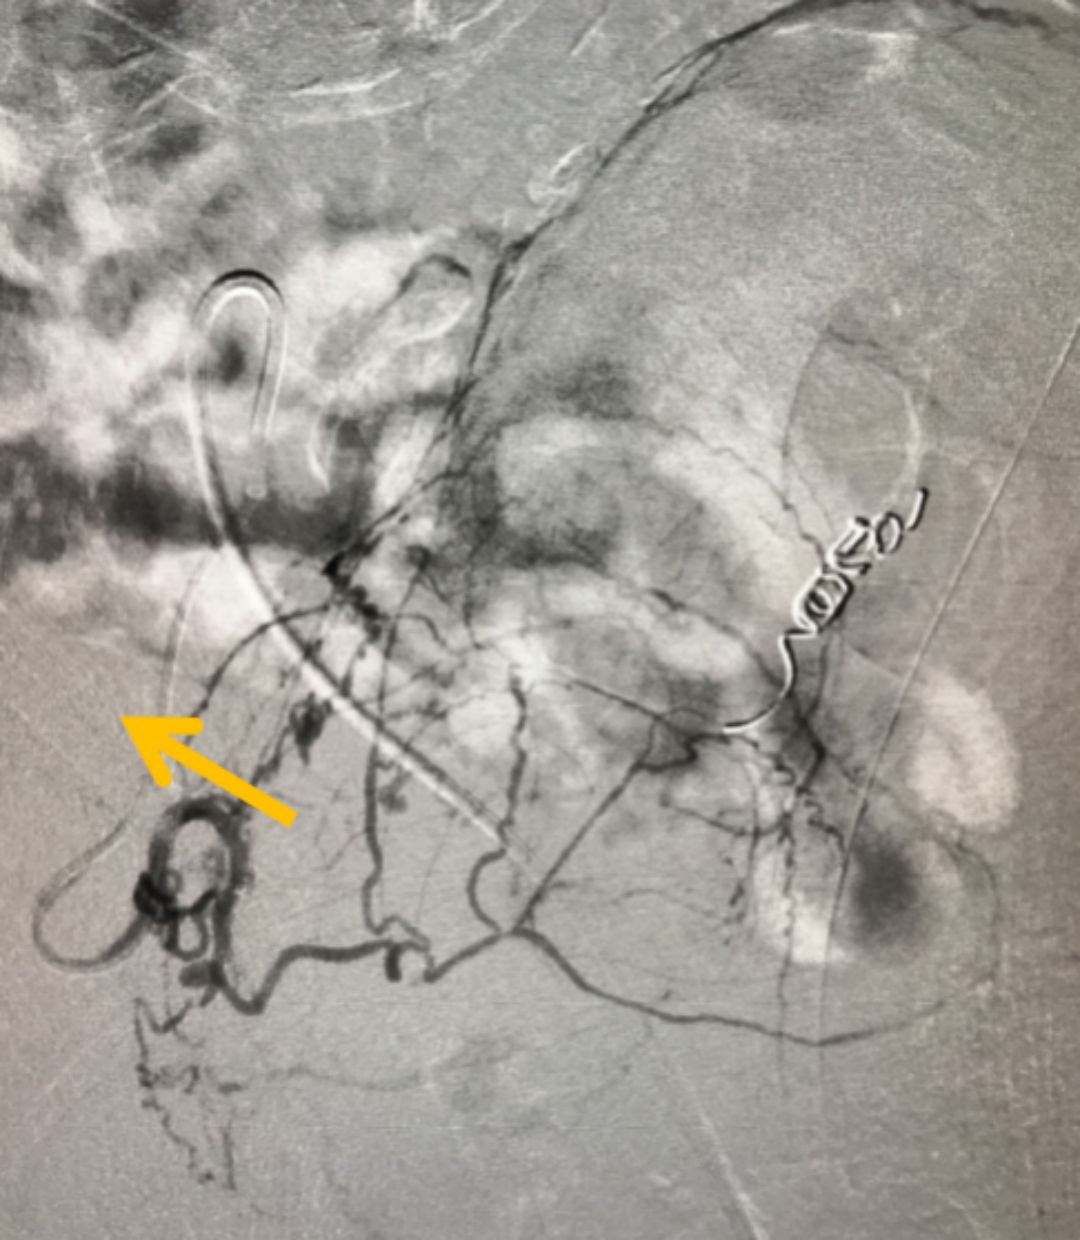

在全面評估后,團隊為他制定了PAE的精準治療方案。手術僅通過大腿根部一個針眼大小的穿刺點,將比頭發絲還細的微導管,在影像引導下精準送入供養前列腺的動脈,并注入安全的栓塞微粒。這個過程,就像精準地“斷糧”

圖:微導管(箭頭所指)

增生的前列腺組織需要充足的血液供應才能維持“生長”。PAE技術的核心,就是阻斷這些供給增生的“營養通道”,從而讓過度增殖的組織因“饑餓”而自然萎縮、壞死,解除對尿道的壓迫。